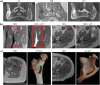

Methods: MR and CT images of nine patients with pelvic and femoral metastases were retrospectively analyzed in this study. The metastatic lesions were osteolytic, osteoblastic or mixed. sCT were generated from pre-treatment or treatment MR images using a UNet-like neural network. sCT was qualitatively and quantitatively compared to CT in the bone (pelvis or femur) containing the metastasis and in a region of interest placed on the metastasis itself, through mean absolute difference (MAD), mean difference (MD), Dice similarity coefficient (DSC), and root mean square surface distance (RMSD).

Results: The dataset consisted of 3 osteolytic, 4 osteoblastic and 2 mixed metastases. For most patients, the general morphology of the bone was well represented in the sCT images and osteolytic, osteoblastic and mixed lesions could be discriminated. Despite an average timespan between MR and CT acquisitions of 61 days, in bone, the average (± standard deviation) MAD was 116 ± 26 HU, MD - 14 ± 66 HU, DSC 0.85 ± 0.05, and RMSD 2.05 ± 0.48 mm and, in the lesion, MAD was 132 ± 62 HU, MD - 31 ± 106 HU, DSC 0.75 ± 0.2, and RMSD 2.73 ± 2.28 mm.

Conclusions: Synthetic CT images adequately depicted the cancellous and cortical bone distribution in the different lesion types, which shows its potential for MRI-HIFU treatment planning.